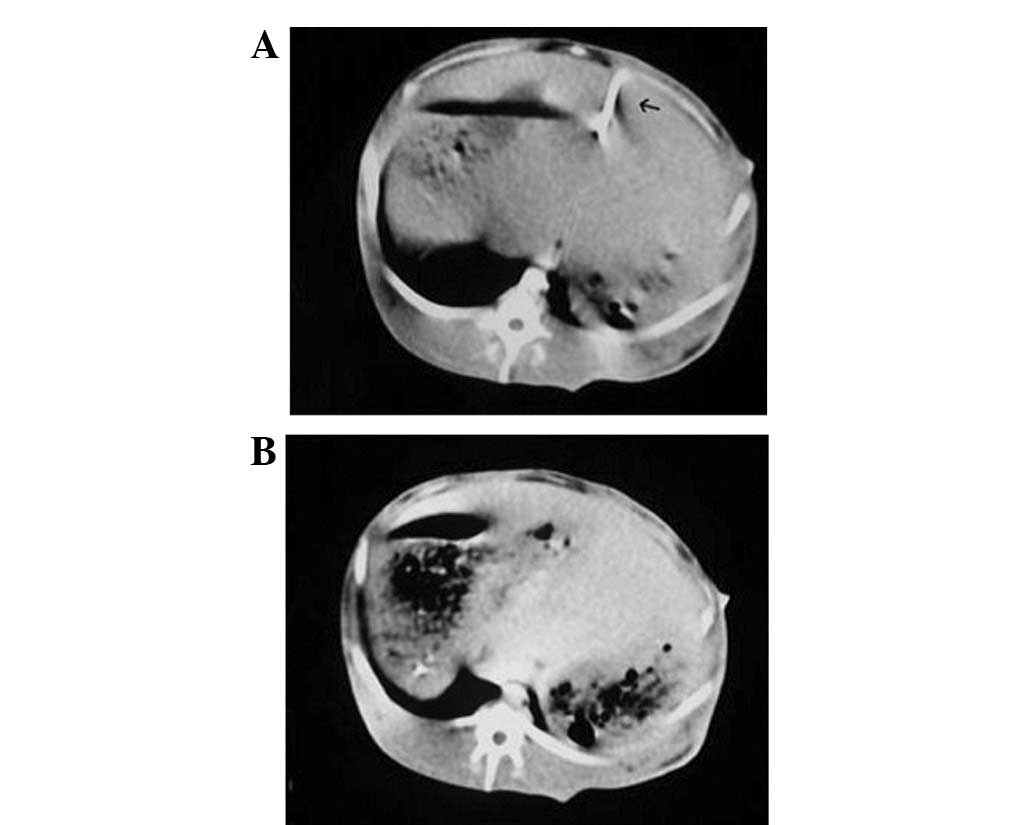

With B-ultrasound monitoring the liver of each rabbit, we chose the rabbits with only one tumor implanted in the left liver lobe and its diameter was measured as 2 cm within 14 to 26 days after tumor implantation. CT plain scanning images revealed a tumor (diameter 2 cm) with low density in the liver of an experimental rabbit (Fig. 1A) and CT enhancement scanning images (Fig. 1B) demonstrated that the tumor had a low-density central region without intensification but the surrounding region of the tumor intensification. MRI showed the VX2 tumor with a high-intensity signal by diffusion imaging, allowing clear visualization of the boundary. No clear signs of central necrosis were shown on B-ultrasound when the tumor sizes were almost 20 mm. This was also verified by CT contrast imaging (Fig. 1B) and MRI diffusion imaging (Fig. 2).

Figure 1.

Three weeks after VX2 cell implantation, (A) the computed tomography (CT) plain scanning image demonstrated a tumor (diameter 2 cm) with low density (white arrow) in the liver of an experimental rabbit and (B) CT enhancement scanning image demonstrated the central region of the tumor without intensification but the surrounding region of the tumor intensification